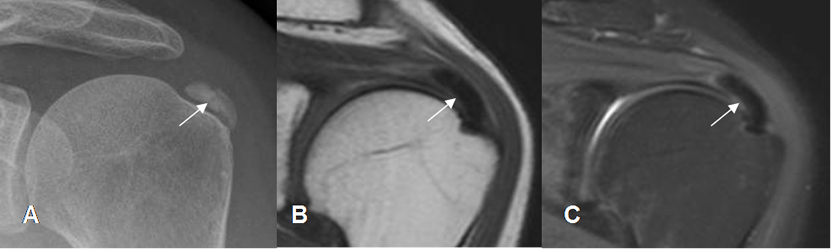

Fig 141. Tendinitis calcificada del supraespinoso.

A: Rx AP de Hombro. Calcificación sobre el tercio distal del tendón del supraespinoso, por tendinitis crónica.

B: RM coronal en T1 y C: RM coronal en STIR. Zona con ausencia de señal en el tercio distal del supraespinoso, que corresponde a la calcificación gruesa.